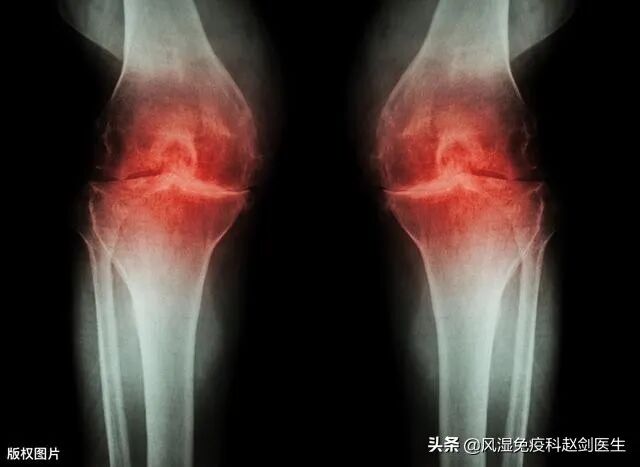

骨关节炎是一种以软骨的变性、破坏及骨质增生为特征的慢性关节病,对于已经发生退行性骨关节炎的患者来说,延缓或阻断关节炎的进展是最重要的,也是治疗的目的所在。

骨关节炎的发生要从软骨的磨损说起,从一开始的轻微病变,发展到关节遭到严重破坏,会有一个漫长的过程。而早期的骨关节炎,如果能及时合理的治疗,病情是可以得到控制不继续加重的。